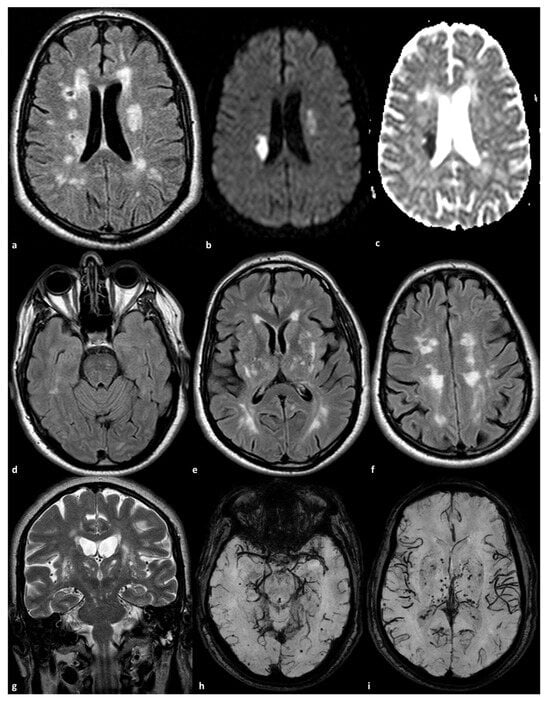

- Lopez-Navarro, E.R.; Mayer, S.V.; Barreto, B.R.; Strobino, K.H.; Spagnolo-Allende, A.; Bueno, P.G.; Gurel, K.; Kozii, K.; Rahman, S.; Khasiyev, F.; et al. Assessing changes on large cerebral arteries in CADASIL: Preliminary insights from a case-control analysis. J. Stroke Cerebrovasc. Dis. 2025, 34, 108294. [Google Scholar] [CrossRef]

- Zhang, C.; Li, W.; Li, S.; Niu, S.; Wang, X.; Yu, X.; Zhang, Z. Intracranial Large Artery Abnormalities and Association with Cerebral Small Vessel Disease in CADASIL. Front. Neurol. 2020, 11, 726. [Google Scholar] [CrossRef]